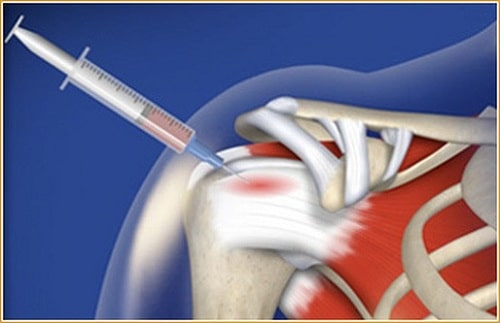

- بهترین آزمایشات موجود برای تشخیص پارگی لابروم، یک اسکن رزونانس مغناطیسی (MRI) یا یک تست به نام CT-arthrogram است (این تست یک تست CAT قبل از آرتروگرام بوده که در آن رنگ به داخل شانه تزریق می شود).

درمان با سلولهای بنیادی

روش درمان با سلولهای بنیادی میتواند جایگزین ایدهآل جراحی برای درمان آسیبهای ورزشی و اختلال حاد شانه باشد.درمان با سلولهای بنیادی میتواند جایگزین ایدهآل برای افرادی باشد که از درد ناشی از آسیب به غضروف مفصلی به دلیل بیماری حاد، آسیب، التهاب و یا اضافه بار (شانه) شانه رنج میبرند. این میتواند گزینهای مناسبتر از عمل آرتروسکوپی شانه یا جراحی جایگزینی شانه باشد زیرا چنین روشهای جراحی اغلب پیچیده است و ممکن است به دلایل متعددی اثر دلخواه را نداشته باشد، مانند بیومکانیک پیچیده مفصل شانه. علاوه بر این، پس از عمل جراحی، یک روند طولانی توانبخشی به منظور بازگرداندن تحرک کامل به وجود میآید.